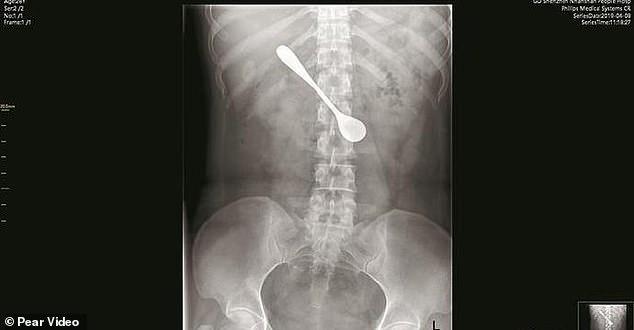

Ii Rămăsese Un Os De Pește In Gat La Masă Așa Că A Decis Să L